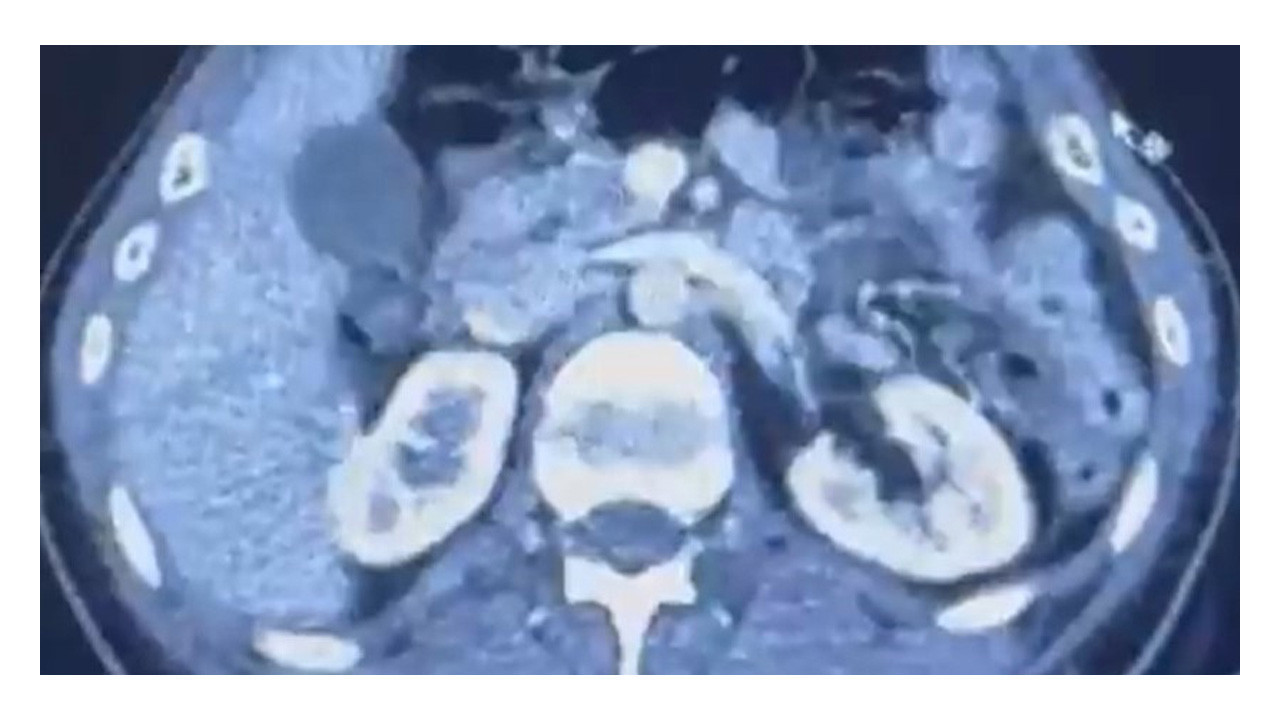

Edinilen bilgiye göre Narkotik Suçlarla Mücadele Şube Müdürlüğü ekiplerince uluslararası uyuşturucu madde ticareti yapan kurye şahıslara yönelik gerçekleştirilen çalışmalarda, İran’dan Türkiye'ye uyuşturucu madde getirdiği tespit edilen şüpheli şahısların yakalanması amacıyla operasyon düzenlendi. Düzenlenen operasyonda; S.C., R.B.C. ve G.M. yakalandı. S.C. ve R.B.C.'nin Kayseri Şehir Hastanesi'nde yapılan iç beden muayenelerinde, mide kısımlarında bulunduğu tespit edilen 50 adet kapsül şeklinde toplam 554 gram uyuşturucu madde ele geçirildi. Şüpheliler gözaltına alınarak haklarında 'Uyuşturucu Madde Ticareti Yapmak' işlem başlatıldı.